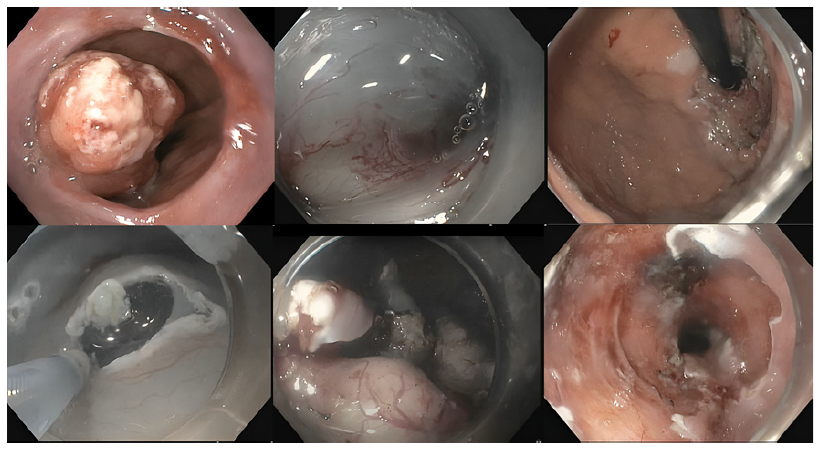

A 58-year-old female, with a medical history of stage IIB Hodgkin lymphoma in remission for over 5 years post-chemoradiation, and treated invasive breast and renal carcinomas, was incidentally diagnosed with a cardiac gastric polyp on a follow-up computed tomog-raphy (CT). Upper endoscopy and endoscopic ultrasound (EUS) revealed a 50 mm ulcerated polypoid subepithelial lesion (Fig. 1) originating from a small stalk in the muscularis propria (MP). Biopsies and fine-needle biopsy were inconclusive but without epithelial neoplastic tissue. Subsequent staging showed no lymph nodes or distant metastasis. Given the high morbidity associated with surgery - total gastrectomy - the tumor’s small insertion in the MP, the patient’s lack of lymph node involvement or distant metastasis, and their preference for a less invasive approach, endoscopic submucosal dissection (ESD) was chosen as the optimal treatment option. En bloc ESD was performed without technical difficulties, revealing the lesion’s superficial origin in the MP (Fig. 2), which eliminated the need for perforation and subsequent defect closure. However, because of its dimension and shape, the specimen was fragmented during retrieval. Histological analysis confirmed gastric leiomyosarcoma with non-evaluable margins (Fig. 3). Following multidisciplinary discussion, surveillance was recommended. At 12-month follow-up, the patient remains with no signs of recurrence at CT and endoscopic evaluation.

Fig. 2 Endoscopic submucosal dissection (ESD) procedure illustrating the initial lesion and key procedural steps, including the circumferential incision and submucosal dissection. This figure highlights the lesion at the start, the progression of the ESD, and the final appearance of the mucosal defect.